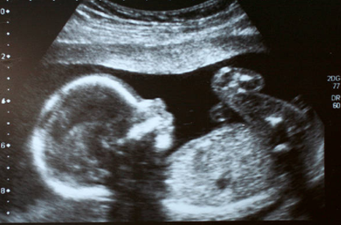

Pregnancy

By Trine Jensen-Burke